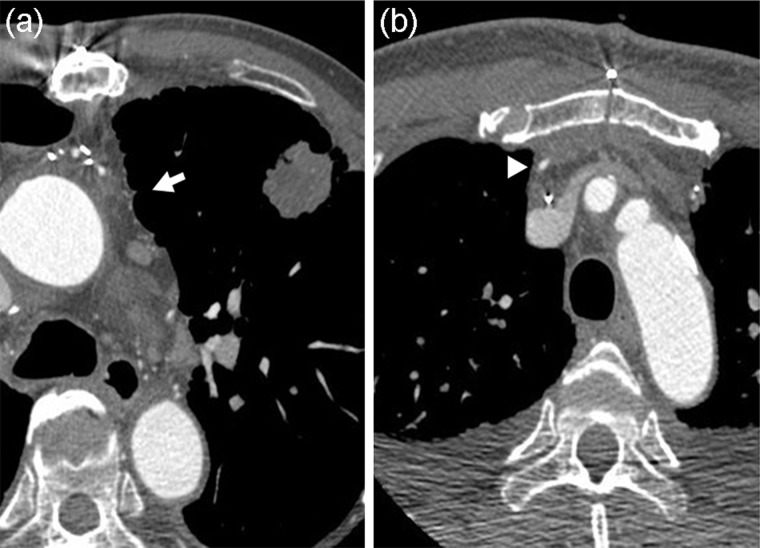

Figure 1:

Preoperative chest CT findings. (a) Case 1: white arrow indicates possible adhesion to ITA graft pedicle and left upper lobe. (b) Case 2: white arrow head indicates the ITA graft.